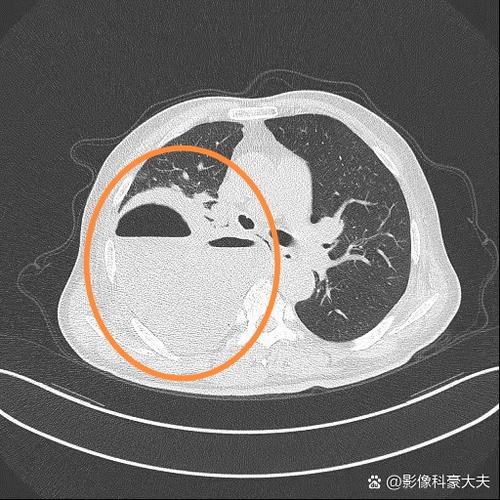

- 影像学改变:胸部CT是确诊的金标准,可以看到肺部有新的炎症浸润影(斑片状阴影)。